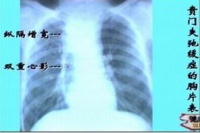

2.胸部平片 本病初期,胸片可无异常。随着食管扩张,可在后前位胸片见到纵隔右上边缘膨出。在食管高度扩张、伸延与弯曲时,可见纵隔增宽而超过心脏右缘,有时可被误诊为纵隔肿瘤。当食管内潴留大量食物和气体时,食管内可见液平。大部分病例可见胃泡消失。